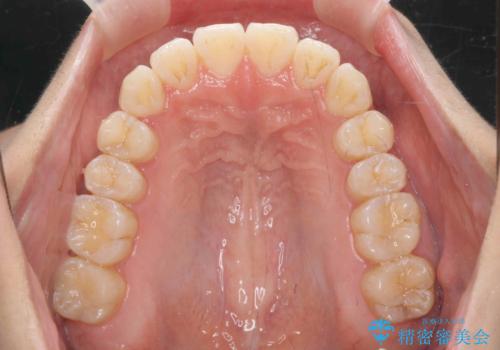

- 前歯の噛み合わせの開きの改善を求めて来院されました。

奥歯はほとんど動かさず(奥歯の噛み合わせはほとんど変えず)前歯のIPR矯正でガタつき前突感(出っ歯感)の改善を計画します。

ほとんど前歯のみの矯正治療であることからトータル14枚のマウスピースで並べるインビザラインライトによる治療を行います。